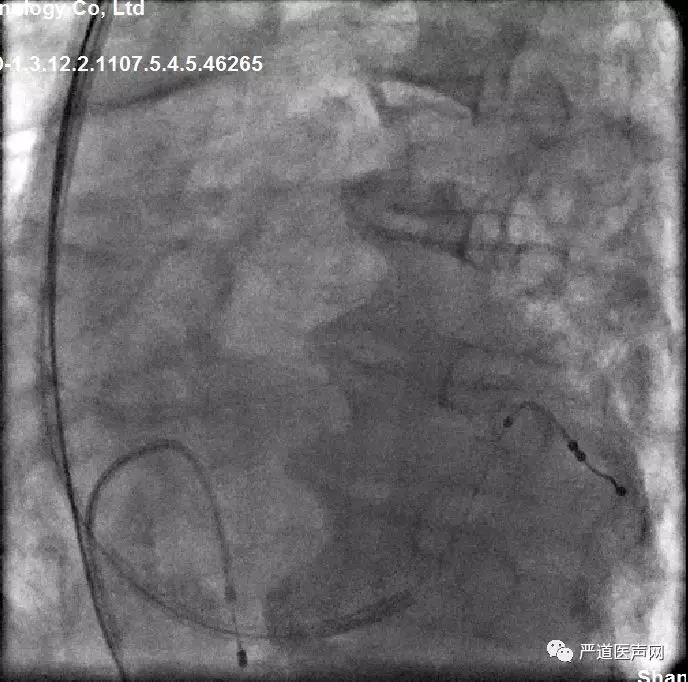

● LAO发现走形左室侧的靶静脉有三根,RAO发现侧静脉两根,但是与主干分支处有迂回夹角

RAO